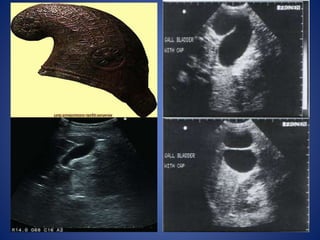

Phrygian Cap

Phrygian cap is the most common abnormality of gallbladder shape,

occurring in 1% to 6% of the population.

Named after the headgear worn by ancient Greek slaves as a sign of

liberation.

This deformity is characterized by a fold or septum of the gallbladder

between the body and fundus.

Two variations of this anomaly have been described.

Retroserosal /concealed type,the GB is smoothly invested by peritoneum,

and the mucosal fold that projects into lumen may not be visible externally.

Serosal or visible type, the peritoneum follows the bend in the fundus,

then reflects on itself as the fundus overlies the body.